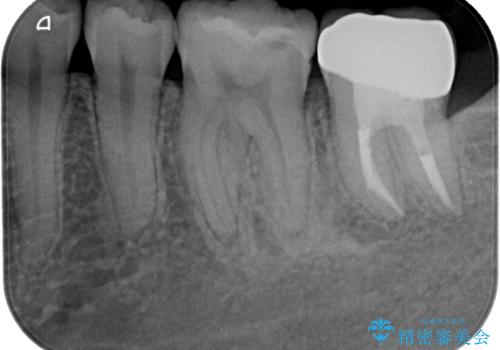

根管治療後は状態を確認し、オールセラミッククラウンにて補綴治療を行うこととしました。

歯根先端付近の歯槽骨が溶けてるレントゲン像が認められましたが、治療から半年後のレントゲン写真では、消退している様子が認められました。